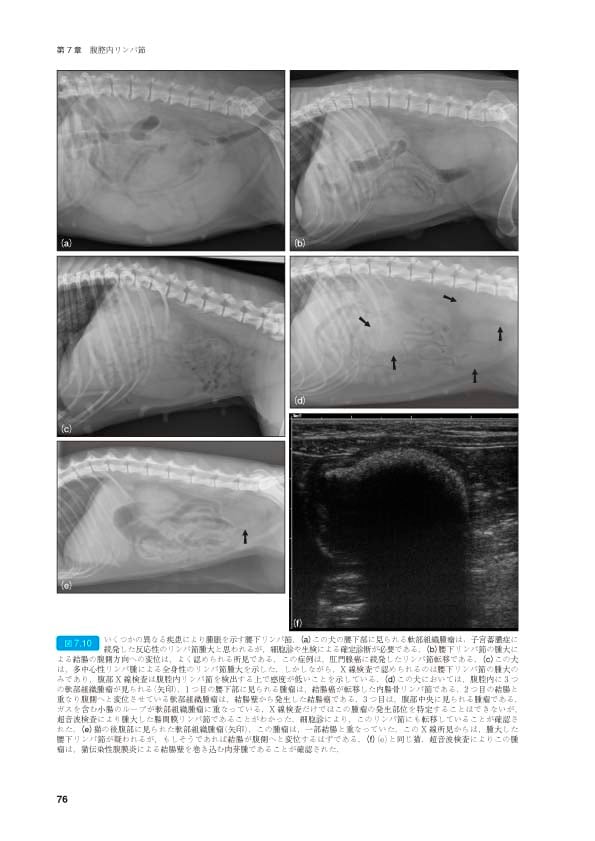

「犬と猫のベーシック画像診断学 画像診断の基礎/胸部編」「犬と猫のベーシック画像診断学 腹部編」「犬と猫のベーシック画像診断学 骨と関節/頭部/脊柱/内分泌器官編」獣医放射線学教育研究会定価: ¥ 10000#獣医放射線学教育研究会 #本 #自然/医療・薬学・健康新品を購入後裁断、スキャンを行ったものです(自炊済み)。その後現品の使用はありません。ご理解いただける方のみご購入をお願いいたします。